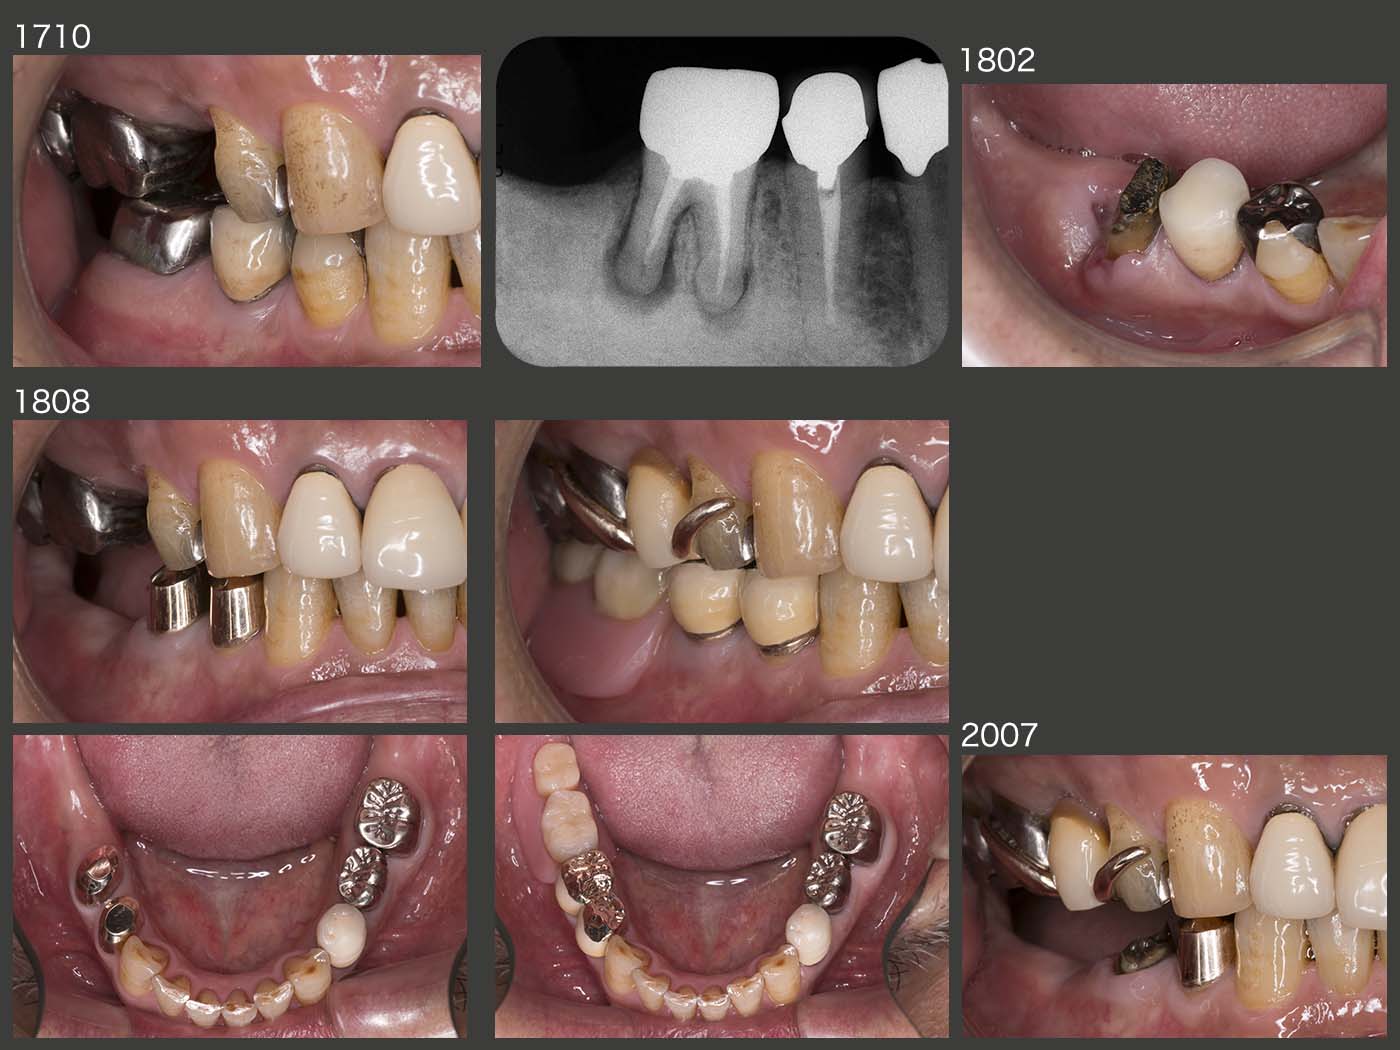

2017年10月,右下6の咬合時痛で来院.デンタルX線写真から遠心根の歯根破折と診断し,18年1月,ヘミセクションした.しかし,2月になっても,近心根の圧痛等が改善せず,歯周ポケットも10mmみられるようになったため,近心根も抜去した.なお,抜歯時,歯根の破折線を確認した.18年8月,右下4および5を支台歯とするコーヌス義歯を装着した.20年7月,右下5の内冠がコアごと脱離し,再合着した.コアを作り替えずに,内冠を製作したが,ポストの長さが足りなかったと反省している.